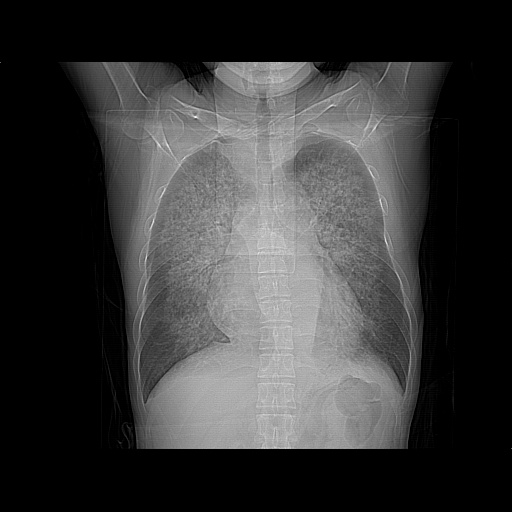

男、42岁、咯血3天。既往有甲亢、贫血、血尿蛋白尿史多年。血象:wbc:6.   中性粒:70.6%。

结合病史考虑双肺泡积血,双侧胸腔少量积液;肺水肿待排(肺水肿症状重)。

双肺堆成磨玻璃影,双测胸腔积液。考虑:肺水肿、间质性肺炎、真菌感染、ards、hiv感染、肺出血。

双肺野对称性磨玻璃影,分布于内中带,双侧胸水,患者有咯血。

双肺野广泛对称性磨玻璃影、实变影,以肺门为中心,主要分布于内中带,符合典型肺泡性肺水肿;伴双侧胸腔少量游离积液。结合患者既往病史且咯血就诊,支持多因素(尿毒症等)所致之肺水肿、肺出血、胸水;影像表现暂不考虑心源性水肿,且症状也不太符。需密切随诊结合临床治疗等进一步明确。

心影增大密度略低,双肺磨玻璃样高密度影及双侧胸腔积液,考虑心功能不全继发双肺肺水肿及双侧胸腔积液。心影密度略低,考虑贫血所致。